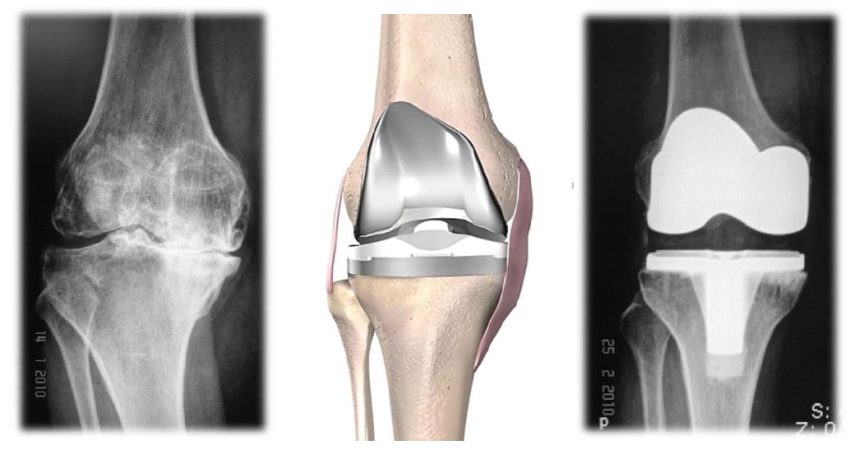

การผ่าตัดเปลี่ยนข้อเข่าเทียมในผู้ป่วยโรคข้อเข่าเสื่อม

การผ่าตัดเปลี่ยนข้อเข่าเทียมคืออะไร คือการผ่าตัดเพื่อนผิวข้อเข่าเดิมที่เสื่อมสภาพออก และทดแทนผิวข้อใหม่ด้วยข้อเข่า เทียม ควรพิจารณาผ่าตัดเปลี่ยนข้อเข่าเทียมเมื่อใด ผู้ป่วยโรคข้อเข่าเสื่อมที่รับการรักษาด้วยวิธีการไม่ผ่าตัด

การผ่าตัดเปลี่ยนข้อเข่าเทียมแบบแผลเล็กและเนื้อเยื่อบาดเจ็บน้อย

การผ่าตัดแบบแผลเล็กและเนื้อเยื่อบาดเจ็บน้อยคืออะไร การผ่าตัดเปลี่ยนข้อเข่าเทียมช่วยให้ผู้ป่วยที่มีความทุกข์ทรมานจากโรคข้อเข่าเสื่อม กลับมาใช้ชีวิตได้อย่างมีความสุขอีกครั้งหนึ่งวิธีการผ่าตัดมาตรฐานแบบดั้งเดิมให้ผลที่ดีเป็นที่